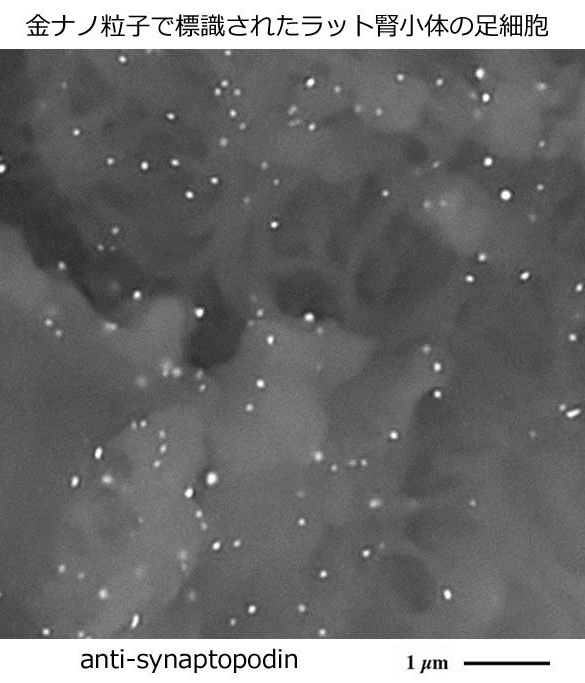

デスクトップ型低真空走査電子顕微鏡の利点・特性を活かした

生体物質の局在を可視化する新たな金ナノ粒子標識法の開発

In situ strategy for biomedical target localization via nanogold nucleation and secondary growth

酵素抗体法を用いて免疫組織化学染色された光顕用パラフィン切片に塩化金酸処理を施して形成された金ナノ粒子を成長させ、標的生体物質の局在を電子顕微鏡で容易に可視化する新たな金ナノ粒子標識法を開発しました。

新たな金ナノ粒子標識法の開発

Sawaguchi, A., Kamimura, T., Takahashi, N., et al. In situ strategy for biomedical target localization via nanogold nucleation and secondary growth.

Commun Biol. 4(1):710, 2021 Open Access

DOI: 10.1038/s42003-021-02246-3